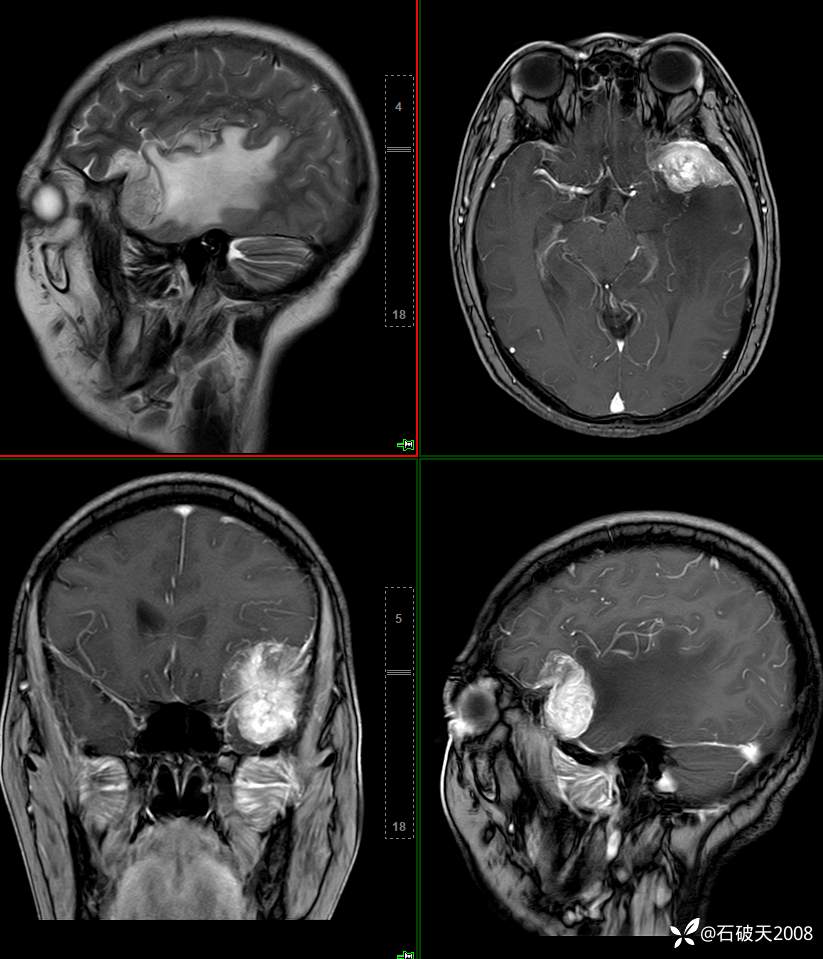

矢状位及增强